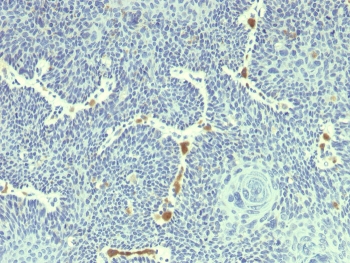

Human papilloma viruses (HPVs) can be classified as either high risk or low risk according to their association with cancer. HPV16 and HPV18 are the most common of the high risk group while HPV6 and HPV11 are among the low risk types. Approximately 90% of cervical cancers contain HPV DNA of the high risk types. Mutational analysis has shown that the E6 and E7 genes of the high risk HPVs are necessary and sufficient for HPV transforming function. The specific interactions of the E6 and E7 proteins with p53 and pRB, respectively, correlate with HPV high and low risk classifications. The high risk HPV E7 proteins bind to pRB with a higher affinity than do the low risk HPV proteins, and only the high risk HPV E6 proteins form detectable complexes with p53 in vitro.

HPV18 E6-β-galactosidase fusion protein was used as the immunogen for this HPV18 E6 antibody.